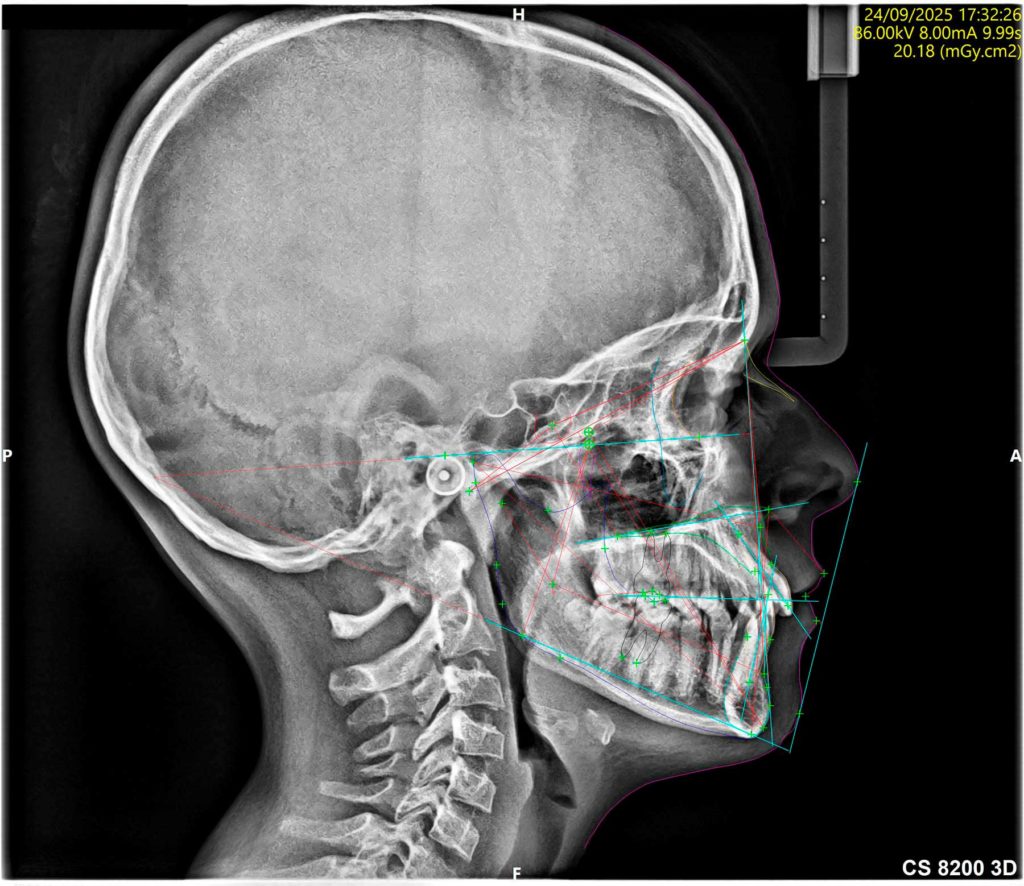

Servicio de Tomografía computarizada CBCT, ortopantomografía, telerradiografía y radiografías de ATM al momento

Mediante la radiología digital de baja radiación, podemos valorar estructuras de interés odontológico o craneal, con imágenes 2D o 3D, según sea el caso.